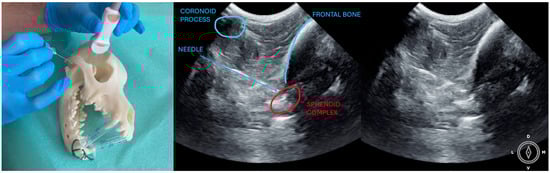

The ultrasound probe was positioned over the temporal region immediately caudal to the orbital ligament to obtain a transverse view of the caudal portion of the pterygopalatine fossa for both approaches. Slight tilting movements adjusted the probe until the following structures were identified: the frontal bone was observed as a hyperechogenic continuous line, which in the deep aspect of the pterygopalatine fossa showed an irregular structure consistent with the sphenoidal complex (optic canal, orbital fissure, and rostral alar canal). The coronoid process was also identified as a sharp, small, strongly reflective, hyperechogenic structure casting a strong acoustic shadow through the fossa (Figure 1 and Figure 2).

Description of coronoid approach: the dog’s mouth was opened with a mouth gag to expose the mandibular notch and facilitate the insertion of the needle from lateral to medial, just ventral to the zygomatic arch and cranial to the temporomandibular joint (Figure 2). The needle was inserted using an in-plane approach, from lateral to medial direction until its tip was positioned near the sphenoidal complex, where the calculated volume was injected.

Figure 2. Position of the probe and the needle. Ultrasound image of the coronoid approach.